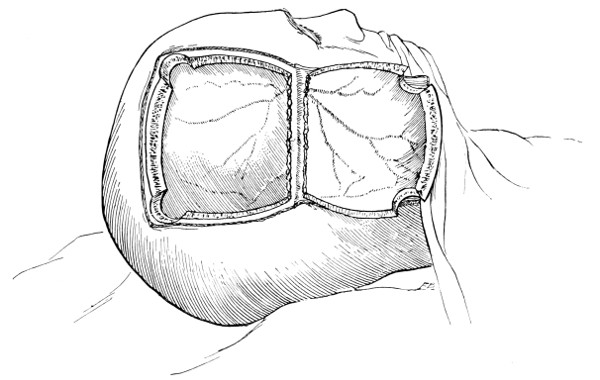

Fig. 18. Second Stage in the Formation of an Osteoplastic Flap. The bone-flap turned down and the dura mater exposed.

Fig. 19. Third Stage in the Formation of an Osteoplastic Flap. The dural flap turned down and the brain exposed. Note the relation of the scalp, bone, and dural incisions to one another.